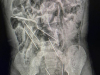

Prema zapisniku Zavoda za sudsku medicinu i kriminalistiku sastavljenom povodom obdukcije mrtvog tijela dječaka, on se liječio u Klinici za dječje bolesti Zagreb zbog metastatskog meduloblastoma, jedne vrste tumora mozga.

Sudsko-medicinski vještaci navode kako je maleni dječak iz Zagorja bolovao od maligne (zloćudne) bolesti centralnog nervnog sistema, dakle od jedne vrste tumora mozga koja se tipično javlja u ranoj dječjoj dobi.

“Bolest je liječena na uobičajeni način: tumor je uklonjen operativnim zahvatom nakon kojeg je provedena kemoterapija prve linije. Postignuta je remisija (zalječenje) bolesti koja je potrajala do listopada druge godine, kada se bolest ponovno javila sa slikom metastaza (udaljenih žarišta) u kanalu kralježnične moždine.

U liječenju ponovne pojave bolesti primijenjena je odgovarajuća kemoterapija druge linije kojom je ponovno postignuto povlačenje bolesti te je nastavljeno s davanjem tzv. visokodozažne terapije. Daljnji terapijski plan uključivao je autolognu transplataciju perifernih matičnih stanica (vraćanje vlastitih, prethodno prikupljenih i obrađenih krvotvornih stanica s ciljem bolje obnove krvne slike).

Kemoterapija predstavlja optimalan, ali ujedno i agresivan oblik liječenja jer sredstva koja se primjenjuju u okviru protokola terapije oštećuju, osim tumorskih, i stanice organizma, među kojima i krvotvorne stanice. Posljedica toga za bolesnika jest pojava brojnih nuspojava (popratnih nepovoljnih učinaka), što je bilo vidljivo i kod dječaka.

Nuspojave koje su se manifestirale bile su tretirane na odgovarajući način. Jedan od terapijskih postupka bilo i davanja krvnog pripravka – koncentrata trombocita. Ovaj pripravak je nadomjestak za manjak trombocita koji dovodi do sklonosti krvarenju. Predmetni krvni pripravak je primijenjen u martu 2018. godine.

Neposredno nakon njegove primjene, nastupilo je naglo i značajno pogoršanje stanja pacijenta te je on kasnije umro”, ističu vještaci.